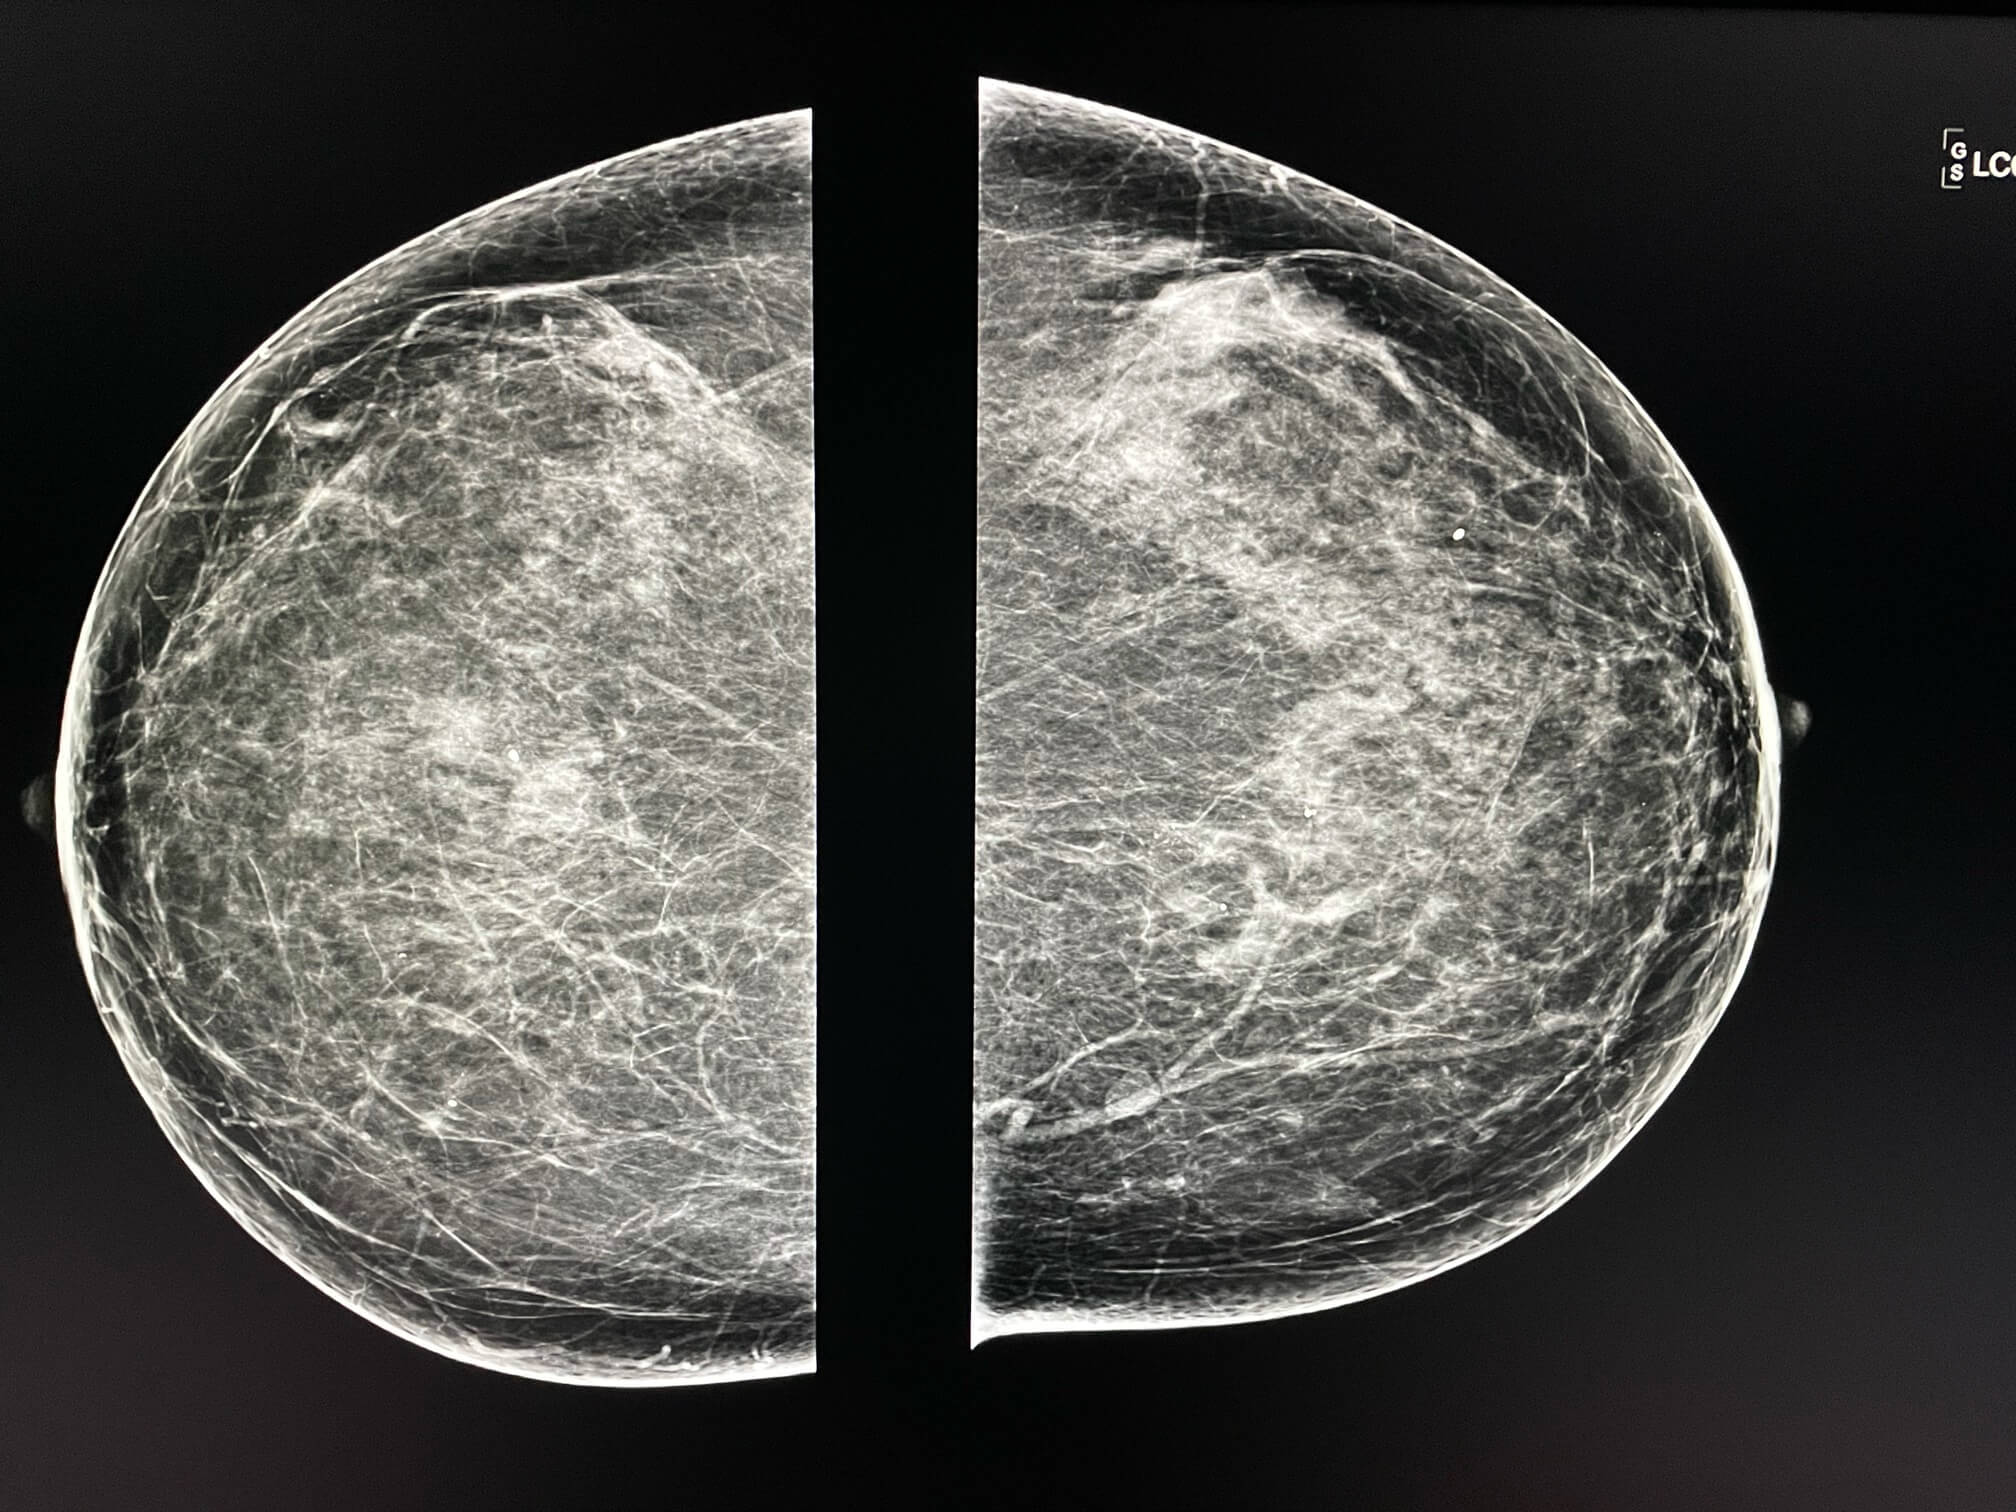

Femme de 63 ans, mammographie de dépistage.

MammoScreen™ pointe en rouge un foyer de microcalcifications retromammelonaires profondes du sein gauche polymorphes. Score MammoScreen 9: examens complémentaires recommandés.

Ce foyer n’existait pas sur la mammographie précédente.

La marcrobiopsie retrouve des lésions de carcinomes intra canalaires.